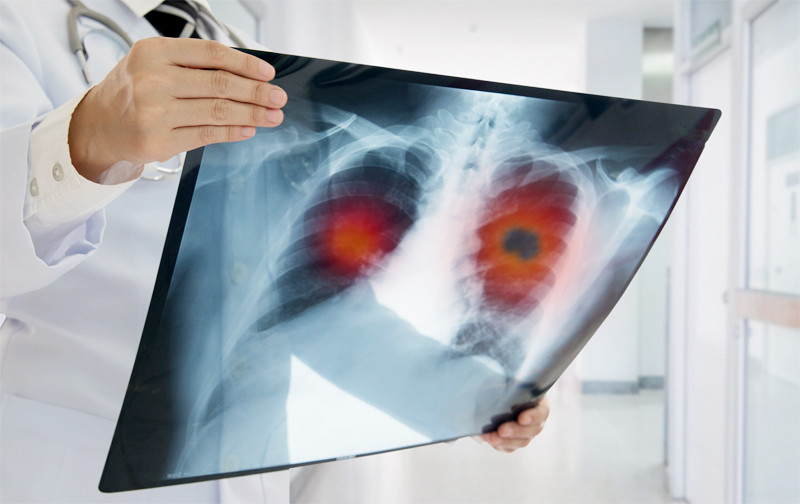

Người đàn ông 45 tuổi đi khám sức khỏe định kỳ, chụp X-quang phát hiện u phổi trái kích thước lớn, vài hôm sau nhận chẩn đoán ung thư.

Nam bệnh nhân đến khám vì ho kéo dài không thuyên giảm. Bác sĩ chụp cắt lớp vi tính phát hiện khối u 2,5cm, ung thư thùy trên phổi bên phải.